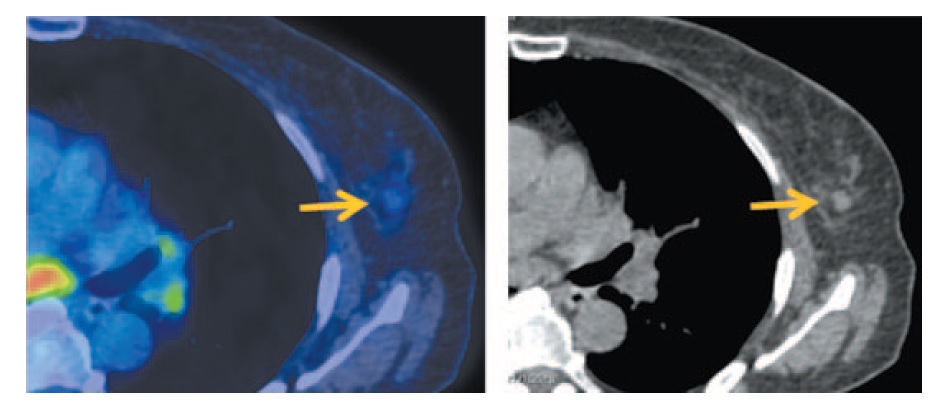

Для установления распространенности опухолевого процесса выполнена ПЭТ/КТ с 18-ФДГ. Определяется увеличение объема щитовидной железы с повышенной фиксацией РФП, стандартизированный коэффициент максимального накопления, SUVmax составил 6,3. Плотность ткани железы снижена. Определяются множественные мелкие, до 6 мм, яремные лимфатические узлы слева II–V групп с диффузной фиксацией РФП, SUVmax 2,35 (рис. 9).

Рис. 9. Больная К., 55 лет. На MIP и аксиальных ПЭТ/КТ проекциях в щитовидной железе с двух сторон определяется увеличение объема ткани с повышенной фиксацией РФП, SUVmax 6,30, плотность ткани снижена, справа метаболическим размером до 29×39×52 мм, слева до 38×48×43 мм, контуры нечеткие. / Fig. 9. A 55-year-old woman. MIP and axial PET/CT images show the enlargement of the thyroid gland tissue on both sides with increased RFP uptake, SUVmax 6.30, the density of tissue is decreased on the right measuring 29×39×52 mm and on the left measuring 38×48×43 mm, the margins are fuzzy.